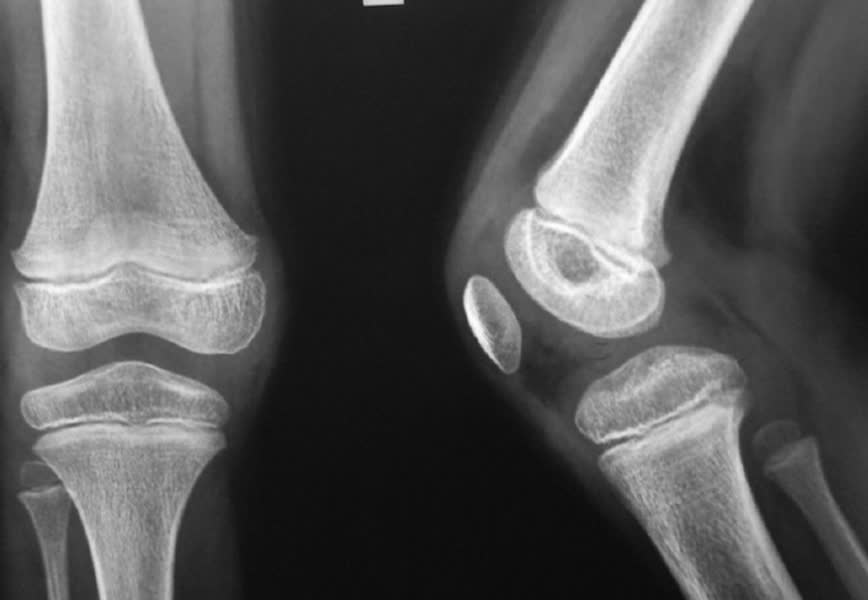

Informatieavond over versleten knie of heup

Honderdduizenden Nederlanders kampen met slijtage aan het knie- of heupgewricht. Pijnlijke aandoeningen, waar veel patiënten onnodig lang mee blijven doorlopen.

Om mensen bekend te maken met een mogelijke oplossing, houdt het Albert Schweitzer ziekenhuis een informatieavond op maandag 9 maart van 19.00 tot 21.00 uur.

Deze vindt plaats in het auditorium van locatie Dordwijk in Dordrecht. Aan bod komen de oorzaak, diagnose en behandeling van knie- en heupslijtage. De orthopeden Joost Peerbooms, Paul de Bruin en Bram van Koeveringe vertellen uitgebreid over de behandelmogelijkheden en operaties. Ook fysiotherapie, de gang van zaken tijdens een ziekenhuisopname en nazorg thuis komen aan bod. Er is volop gelegenheid tot het stellen van vragen.